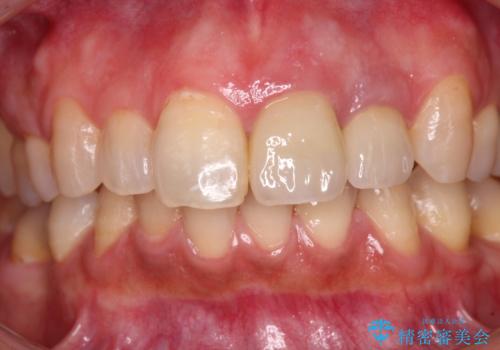

仮歯を装着した時点で、口元が気にならなくなったので、患者様が感じていた違和感の原因は変色した前から2番目の歯であったと思われます。

形態や色彩が左右対称となるように仕上がり、患者様には大変満足していただきました。